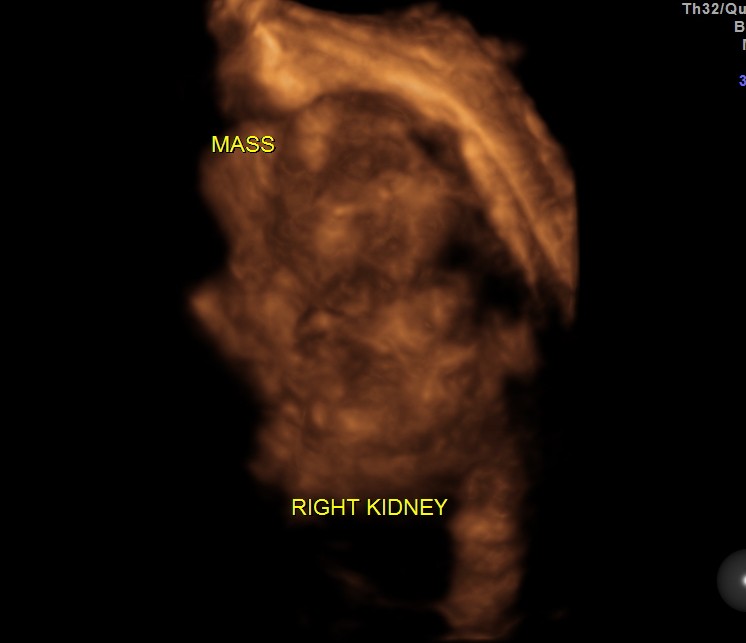

3 D images are given below.

the next is a reconstructed image of the mass.